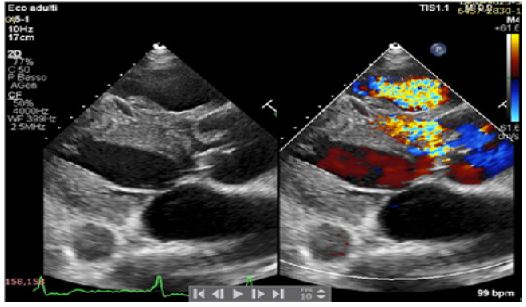

A 42-years old Senegalese man was referred to our department for dyspnea on exertion (NYHA II-III) and clinical signs of heart failure. In his clinical history an undefined cardiopathy, known since childhood but not investigated because asymptomatic, was reported. General examination revealed tachyarrhythmic pulse (rate of 103 per minute) along with normal blood pressure (130/65 mmHg) and arterial oxygen saturation (SpO2 97-99%). Electrocardiography demonstrated atrial fibrillation with left ventricular hypertrophy and signs of pressure overload (Figure 1), while chest X-Ray showed severe cardiomegaly and pulmonary congestion. Transthoracic Echocardiogram (TTE) with color Doppler revealed the presence of a 21 mm perimembranosus Ventricular Septal Defect (VSD), below the aortic valve, with relevant left-to-right shunt (gradient 90 mmHg), partially closed by prolapsing right coronary cusp and accessory tricuspid valve tissue (Figures 2 and 3). A hypertrophied muscle bundle in the mid-ventricular region of the Right Ventricle (RV) along with color-flow turbulence was documented (Figure 4). Due to misalignment, no accurate estimation of intraventricular RV pressure was feasible, but moderate tricuspid regurgitation revealed an atrioventricular gradient of 70 mmHg, suggesting high RV pressures. Other findings were severe aortic valve regurgitation with severe dilation of ascending aorta (diameters of sinuses of Valsalva 60 mm, 28 mm/m2, z-score +6,3, tubular ascending aorta 48 mm, 23 mm/m2, z-score +5,7). 2D and 3 D Transoesophageal Echocardiographic Examination (TOE) confirmed the presence of the anomalous muscle band dividing the RV into two parts: a high-pressure inlet portion and a lower pressure outlet portion (Figures 5 and 6). Severe dilation of both aorta and pulmonary trunk was revealed, confirming severe aortic valve regurgitation with multiple jets and determined by different factors (lack of coaptation, prolapse of the right cusp and distortion of the noncoronary cusp). To accurately measure RV pressures cardiac catheterization was performed. The systolic pressure of the right ventricular inlet and the outlet pressure were 78 and 38 mmHg respectively, determing an intraventricular gradient of 40 mmHg. There was no pressure gradient between the right ventricle outlet tract and the main pulmonary artery (systolic/diastolic/mean pressures were 38/18/25 mmHg respectively). Normal coronary arteries were documented. Patient was scheduled for corrective surgery in the form of resection of the anomalous muscle bundle along with patch closure of the VSD and Bentall procedure for ascending aorta or aortic valve replacement.

Figure 2: Parasternal long axis.

Figure 3: Parasternal long axis.